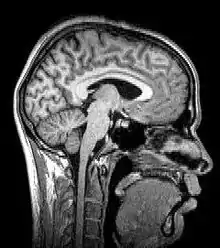

![]() تصوير بالرنين المغناطيسي لشخص مصاب بضخامة الرأس | |

يستخدم التصوير بالرنين المغناطيسي المجال المغناطيسي والأمواج الراديوية لإنتاج صور عالية الجودة لهياكل المخ، ثنائية أو ثلاثية الأبعاد، دون استخدام الإشعاعات المؤينة (الأشعة السينية) أو أجهزة التتبع الإشعاعي.